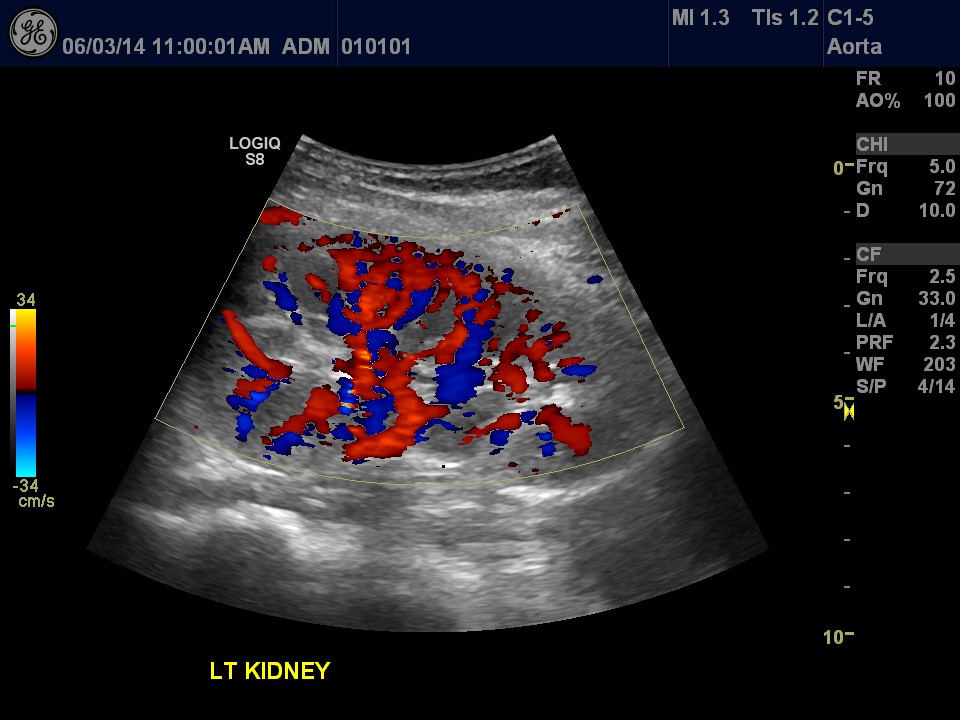

Renal Duplex Examination

When the sonographer assesses the main arteries leading to the kidneys and the kidney tissue, ensuring there is adequate blood flow.

Left Kidney Flow Ultrasound Image